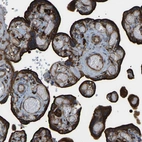

Immunohistochemistry analysis in human placenta and skeletal muscle tissues using HPA019053 antibody. Corresponding PICALM RNA-seq data are presented for the same tissues.